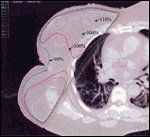

FIGURE 2

Example of the Radiation Isodose Distribution in a Patient With a Large Breast

Cosmesis can be affected by numerous patient, tumor, and technical factors. Some factors that have been shown to have an adverse effect on cosmetic outcome in recent publications include large breast size,[50,52,55] excision volumes exceeding 50 to 100 cm3,[49,51,52,56] extent of axillary surgery,[51,56] postoperative infection or other complications,[ 19,52] and use of a boost to the lumpectomy bed following wholebreast treatment.[52,56] A total radiation dose of more than 5,000 cGy to the breast, greater dose inhomogeneity (Figure 2), and higher fraction sizes (especially to whole-breast volumes) have also been shown to have a negative impact on cosmesis and the risk of complications from radiotherapy.[51,55-57]